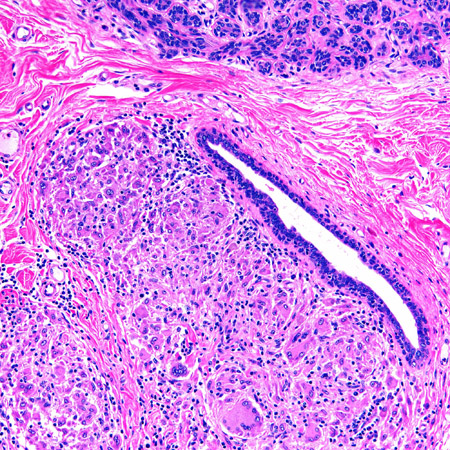

Microscopy image of non-necrotising granulomatous inflammation in the breast

From the collection of Liron Pantanowitz, MD, Tufts University School of Medicine, MA